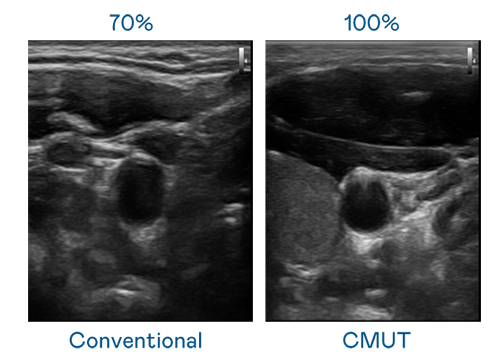

CMUT 技术是一种用电容式微机电元件来产生超音波讯号的技术。与传统 PZT 压电式技术相比,CMUT 频宽增加 30%,更宽频的超音波讯号让影像解析度大幅提升,是实现高影像品质医疗超音波扫描、促进精准医疗发展的关键技术。

大频宽带来超清晰影像

超音波影像的解析度高低,首先取决于探头能发出的讯号频宽。GA黄金甲 CMUT 可提供高清晰的超音波讯号,提供高频宽、高灵敏度、影像纹理细节更高的超音波影像,协助医护人员缩短影像判读时间及利用精准的医疗影像进行诊断。